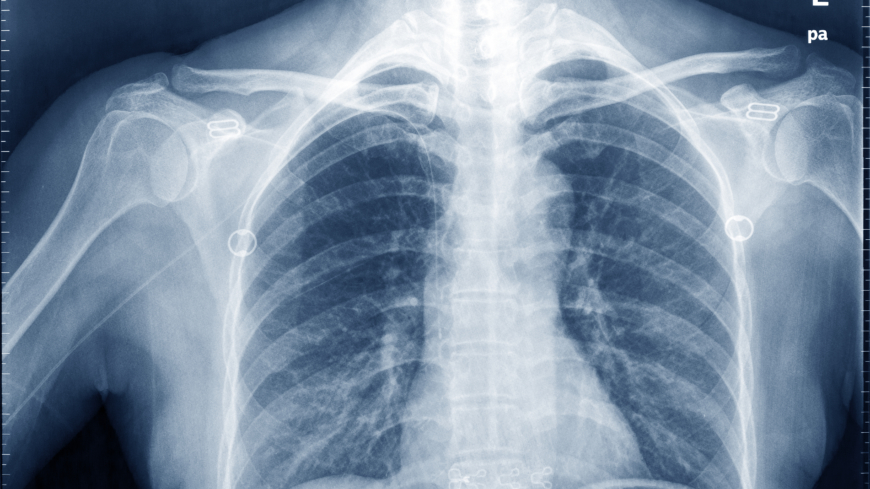

Vi kallar det Röntgenstrålar, men Wilhelm Conrad Röntgen själv tog inget patent på sina konstruktioner och kallade alltid strålarna för X-strålar. Foto: Shutterstock

Röntgenstrålning är en sorts elektromagnetisk strålning (precis som ljus men med en kortare våglängd och mer energi) som lätt passerar genom människokroppen och har lättare att passera genom vävnader än genom benen.